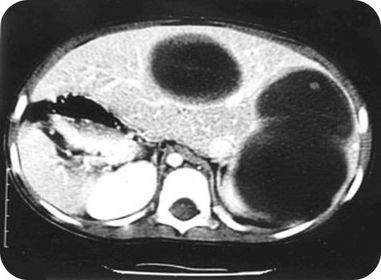

EQUINOCOCOSIS

ENFERMEDAD DE HIGADO POLIQUISTICO

EQUINOCOCOSIS RENAL